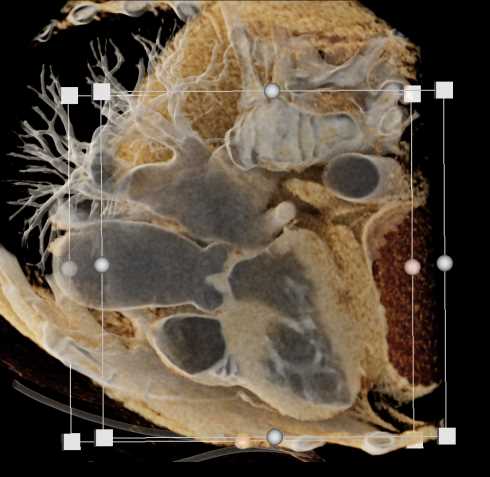

Primary Spindle Cell Carcinoma of the Right Ventricle